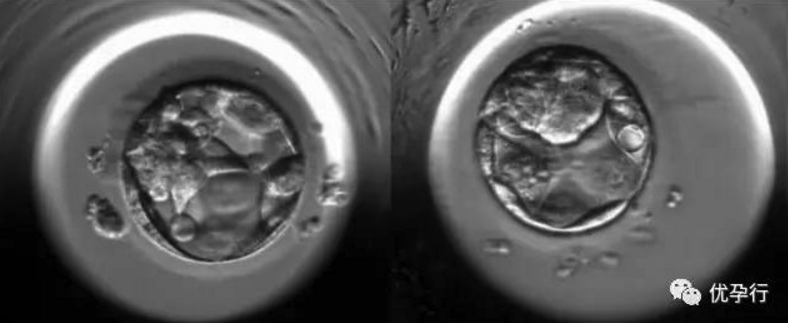

卵子和精子结合后形成受精卵,受精卵由输卵管向子宫运行中,不断进行细胞分裂,此过程称卵,卵裂产生的细胞称卵裂球。随着卵裂球数目的增加,细胞逐渐变小,到第3天时形成一个12~16个卵裂球组成的实心胚,称桑葚胚。在试管婴儿操作中,会将这个在第3天形成的桑葚胚简称为早期胚胎,术前常说的鲜胚指的就是它。

桑葚胚的细胞继续分裂,细胞间逐渐出现小的腔隙,大约2天后它们较后汇合成一个大腔,桑葚胚转变为中空的胚泡。胚泡也就是囊胚,这个时候是受精卵成活的第5天。早期胚胎发育到囊胚的这两天是非常关键的,对温度、空气含氧量、二氧化碳含量的要求都非常高。